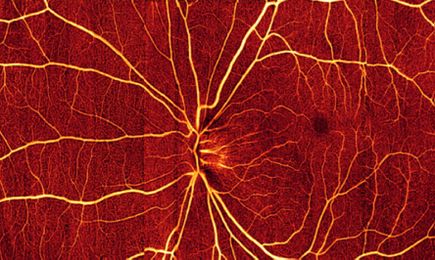

OCT technology has evolved over the past 25 years with great advances in imaging speed and quality. Ophthalmologists can now study disease at the microscopic level without biopsy, and with complete patient comfort. For the first time, eye physicians can visualize and measure blood flow in the smallest of blood vessels, without the need to inject contrast agents. Non-invasive visualization and measurement of blood flow gives great insight into the cause and progression of eye disease.